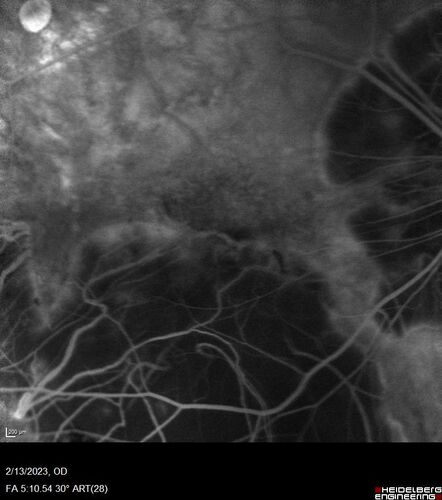

Myopic CNVM Left Eye

80 year old female. VA dropped to 20/125 but improved back up to 20/50 with Vabysmo

Myopic CNVM - Colobomas